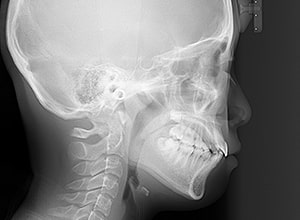

| 口腔内所見 | over jet 3.5mm,over bite4.0mm、下顎正中右側偏位2.0mm、大臼歯関係は左側Ⅰ級であったが、右下6は右下E早期喪失のため近心傾斜しておりⅢ級の臼歯関係となっていた。また上下顎前歯は軽度の叢生を呈していた。 |

| 批評・予后 | 右下5及び7の萌出前に右下6を整直させることによって、右下5の自然萌出が可能となり正常咬合への咬合誘導が行えたと思う。 |